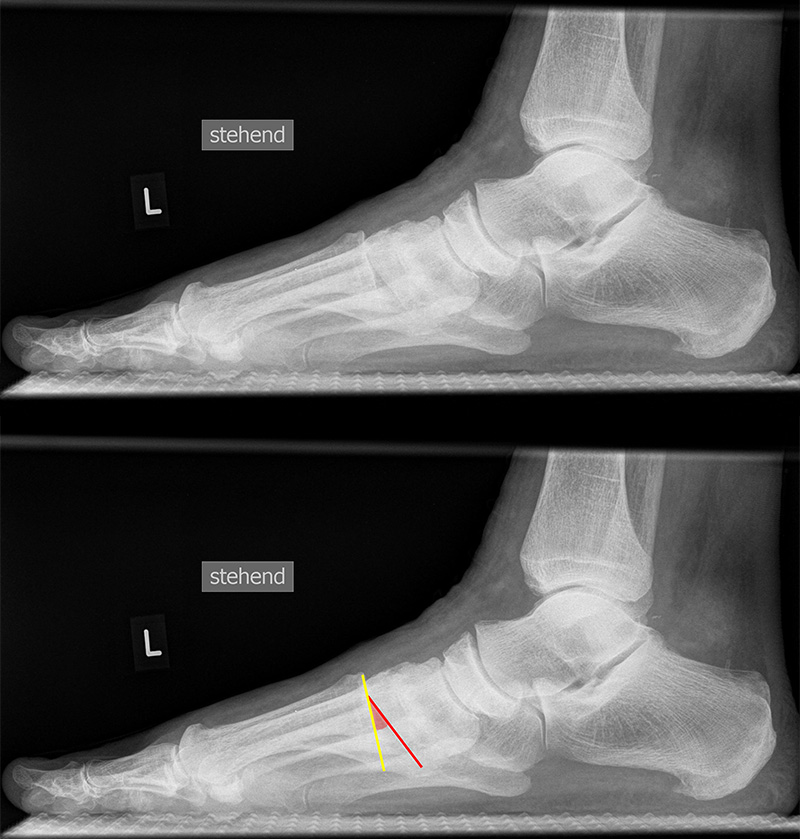

Fuß seitlich mit Belastung

Positionierung:

• Der Patient steht auf beiden Füßen mit gleichmäßiger Lastverteilung.

• Der zur Röntgen der Fuß wird längs des Films positioniert.

• Die Kassette steht senkrecht zum Boden, medial dem Fuß anliegend.

• Der Zentralstrahl wird von lateral nach medial zentriert auf das Kalkaneokuboidalgelenk knapp cranial der Os metatarsale V Basis ausgerichtet.

• Die Röntgenröhre steht 0° horizontal.

Kennzeichen des Röntgenbildes:

• Standardabbildung des Fußes zusammen mit der belasteten d.-p. Aufnahme und der unbelasteten 45° Pronationsaufnahme.

• Überblick über die Fußanatomie und Fußstatik.

• Die seitliche Aufnahme liefert Informationen zur Stabilität des Längsgewölbe und zu den Achsen von Talus, Kalkaneus und Metatarsale I.

• Die Aufnahme wird eingesetzt zur Darstellung von freien Gelenkkörpern sowie knöchernen Veränderungen am Achillessehnenansatz oder der Plantarfaszie.

Besondere Bemerkungen zum Beispielbild:

• Schwere Hallux valgus Deformität.

• Die Sesambeine sind luxiert, ebenso das Großzehengrundgelenk. Luxation des Metatarsophalangealgelenks II.

• Degenerative Veränderungen der tarsometatarsalen (TMT) Gelenkreihe, betont TMT II und III.

Zur Vollansicht und zum Lesen der Bildbeschreibung bitte die Bilder anklicken.

TMT-1-Gelenk lateral (Tarsometatarsale-1-Gelenk)

In der Seitaufnahme wird eine plantare Öffnung des TMT-1-Gelenks als Indikator für eine Instabilität gewertet. Coughlin et al. 5 definierten einen Winkel zwischen der proximalen Gelenkfläche des Os metatarsale I (gelb) und der distalen Gelenkfläche des Os cuneiforme I (rot). (Norm: ±0° 5).

Achsen auf der lateralen Aufnahme

Die Grundlinie (blau) ist definiert durch den tiefsten Punkt der Sesambeine und den tiefsten Punkt des Kalkaneus.

CPA (Calcaneal pitch angle): Der Kalkaneus Inklinationswinkel liegt zwischen der Grundlinie (blau) und der plantaren Begrenzung des Kalkaneus (grün) (Norm 20,8 ± 4,1° 11, 15-39° (Zwipp 2014)).

LTCA (Lateral talocalcaneal angle): Der laterale talokalkaneare Winkel liegt wird gebildet aus der Talusachse (türkis) und einer Verbindungslinie zwischen dem Oberrand des Proc. ant. Calcanei und der dorsalen Begrenzung des Kalkaneus (gelb). (Norm: 33° Range 25-45°) 1213).

LTMA (Lateral talometatarsal angle, Syn. Meary’s angle): Der laterale talometatarsale Winkel wird gebildet aus der Achse des Os metatarsale I (rot) und der Achse des Talus (türkis). (Norm: 7,1 ± 10,8 11).

Böhler-Winkel (Syn. Tubergelenkwinkel)

Es wird eine Linie vom Proc. ant. calcanei zur dorsalen Facette des Subtalargelenks gezogen (rot). Die zweite Linie verläuft von der kranialen Begrenzung des Tuber calcanei zum Subtalargelenk (gelb). Gemessen wird der nach dorsal offene Winkel zwischen den beiden Linien (Norm: 22-48° 9).